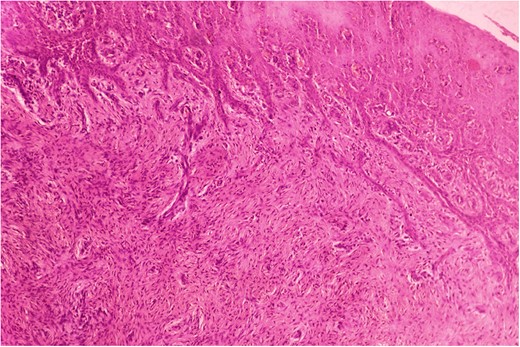

Biopsy was taken from hypertrophied and ulcerated lesion. On microscopy, tissue was lined by keratinized stratified squamous epithelium with surface ulceration. Underlying stroma showed infiltrating squamous cell carcinoma (SCC) along with extensive collagenous fibrosis (Fig. 2). Dense acute and chronic inflammations were also noted. A diagnosis of SCC with familial gingival fibromatosis was given (Fig. 3).

Histopathological picture showing islands of squamous cell carcinoma infiltrating into the stroma. (H&E, ×400).

Histopathological picture showing infiltrating squamous cell carcinoma along with bundles of collagenous fibrous connective tissue. (H&E, ×400).